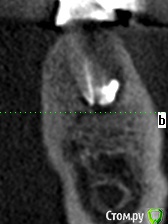

meld Опубликовано 7 ноября, 2017 Автор Поделиться Опубликовано 7 ноября, 2017 Прицельный снимок 38 зуба и его срезы Ссылка на комментарий

IvanK Опубликовано 7 ноября, 2017 Поделиться Опубликовано 7 ноября, 2017 ЗдравствуйтеЕсть периапикальные измененияя за удаление и последующую имплантацию 1 Ссылка на комментарий